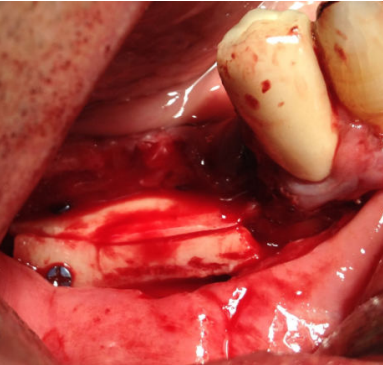

Se planificó la realización de la técnica de Khoury bajo anestesia local y sedación consciente intravenosa. Se realizó una incisión en mucosa libre extendiéndose desde el trígono retromolar hasta el canino homolateral (Figura 3). El colgajo resultante permitió el acceso para la obtención de un injerto en bloque de unos 3 mm de espesor procedente de la línea oblicua externa mandibular del cuadrante homolateral, mediante instrumental piezoeléctrico. La región del trígono retromolar y de la rama ascendente se utilizó para obtener hueso autógeno particulado mediante el uso de un rascador.